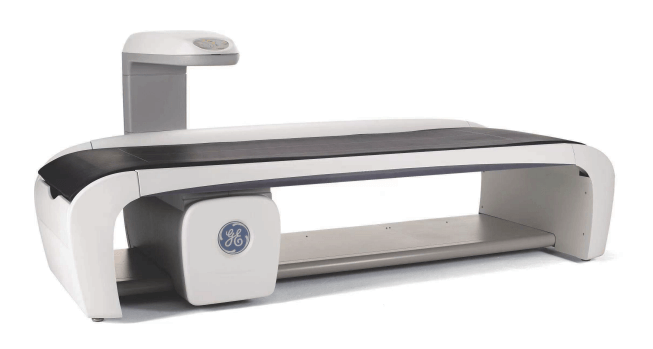

先进检验设备